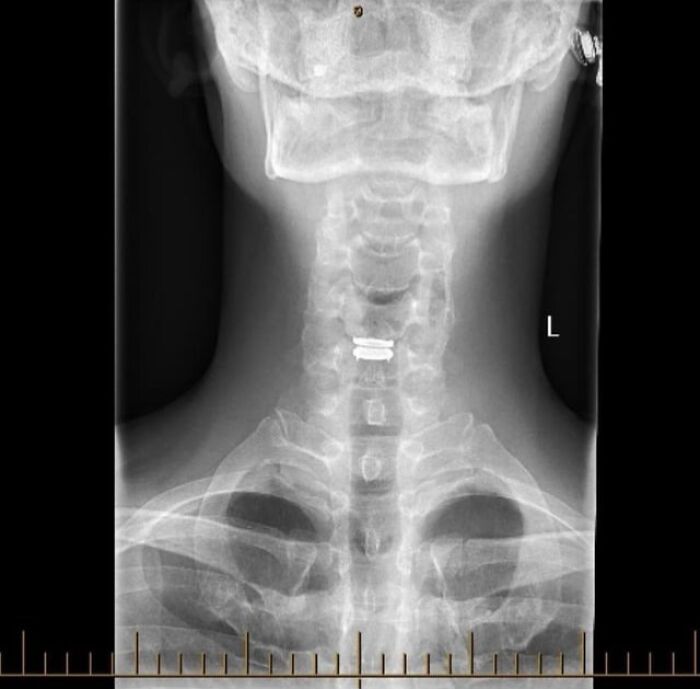

#17 Thought You Good People Might Like To See My New C5/C6 Disc

Image source: medical